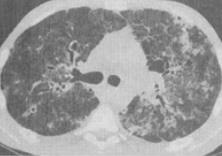

HIV患者咳嗽咳痰1个月余,伴发热,结合图像,最可能的诊断是()。

A、机会性肺部感染

B、卡氏肺囊虫性肺炎

C、卡波济肉瘤

D、肺淋巴瘤

E、间质性肺炎

B